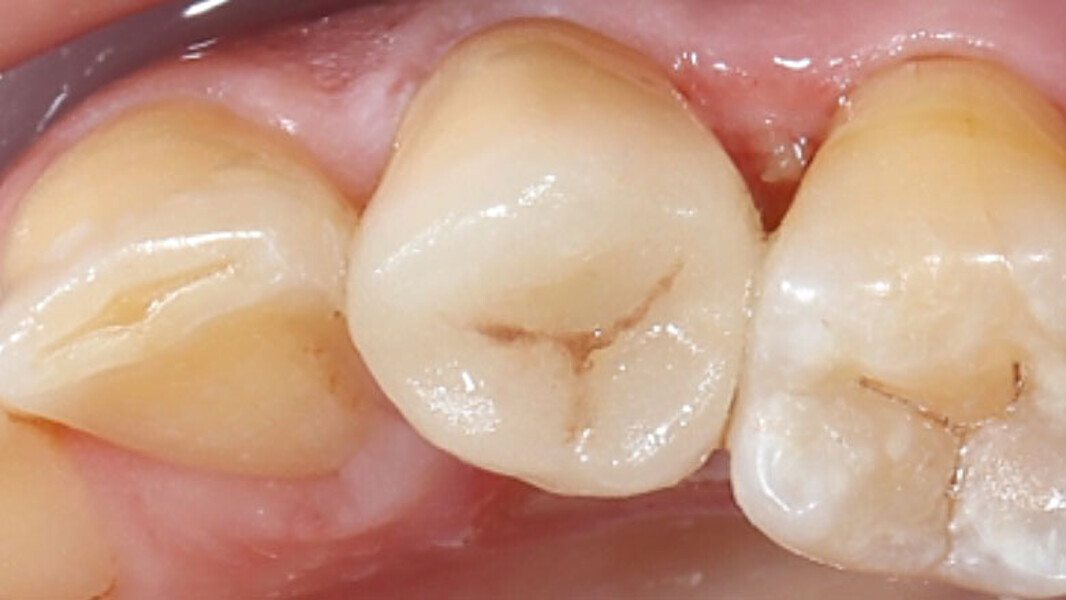

Fig. 1. Situación inicial: el diente 34 estaba fuertemente dañado. La encía se había adentrado en la cavidad.